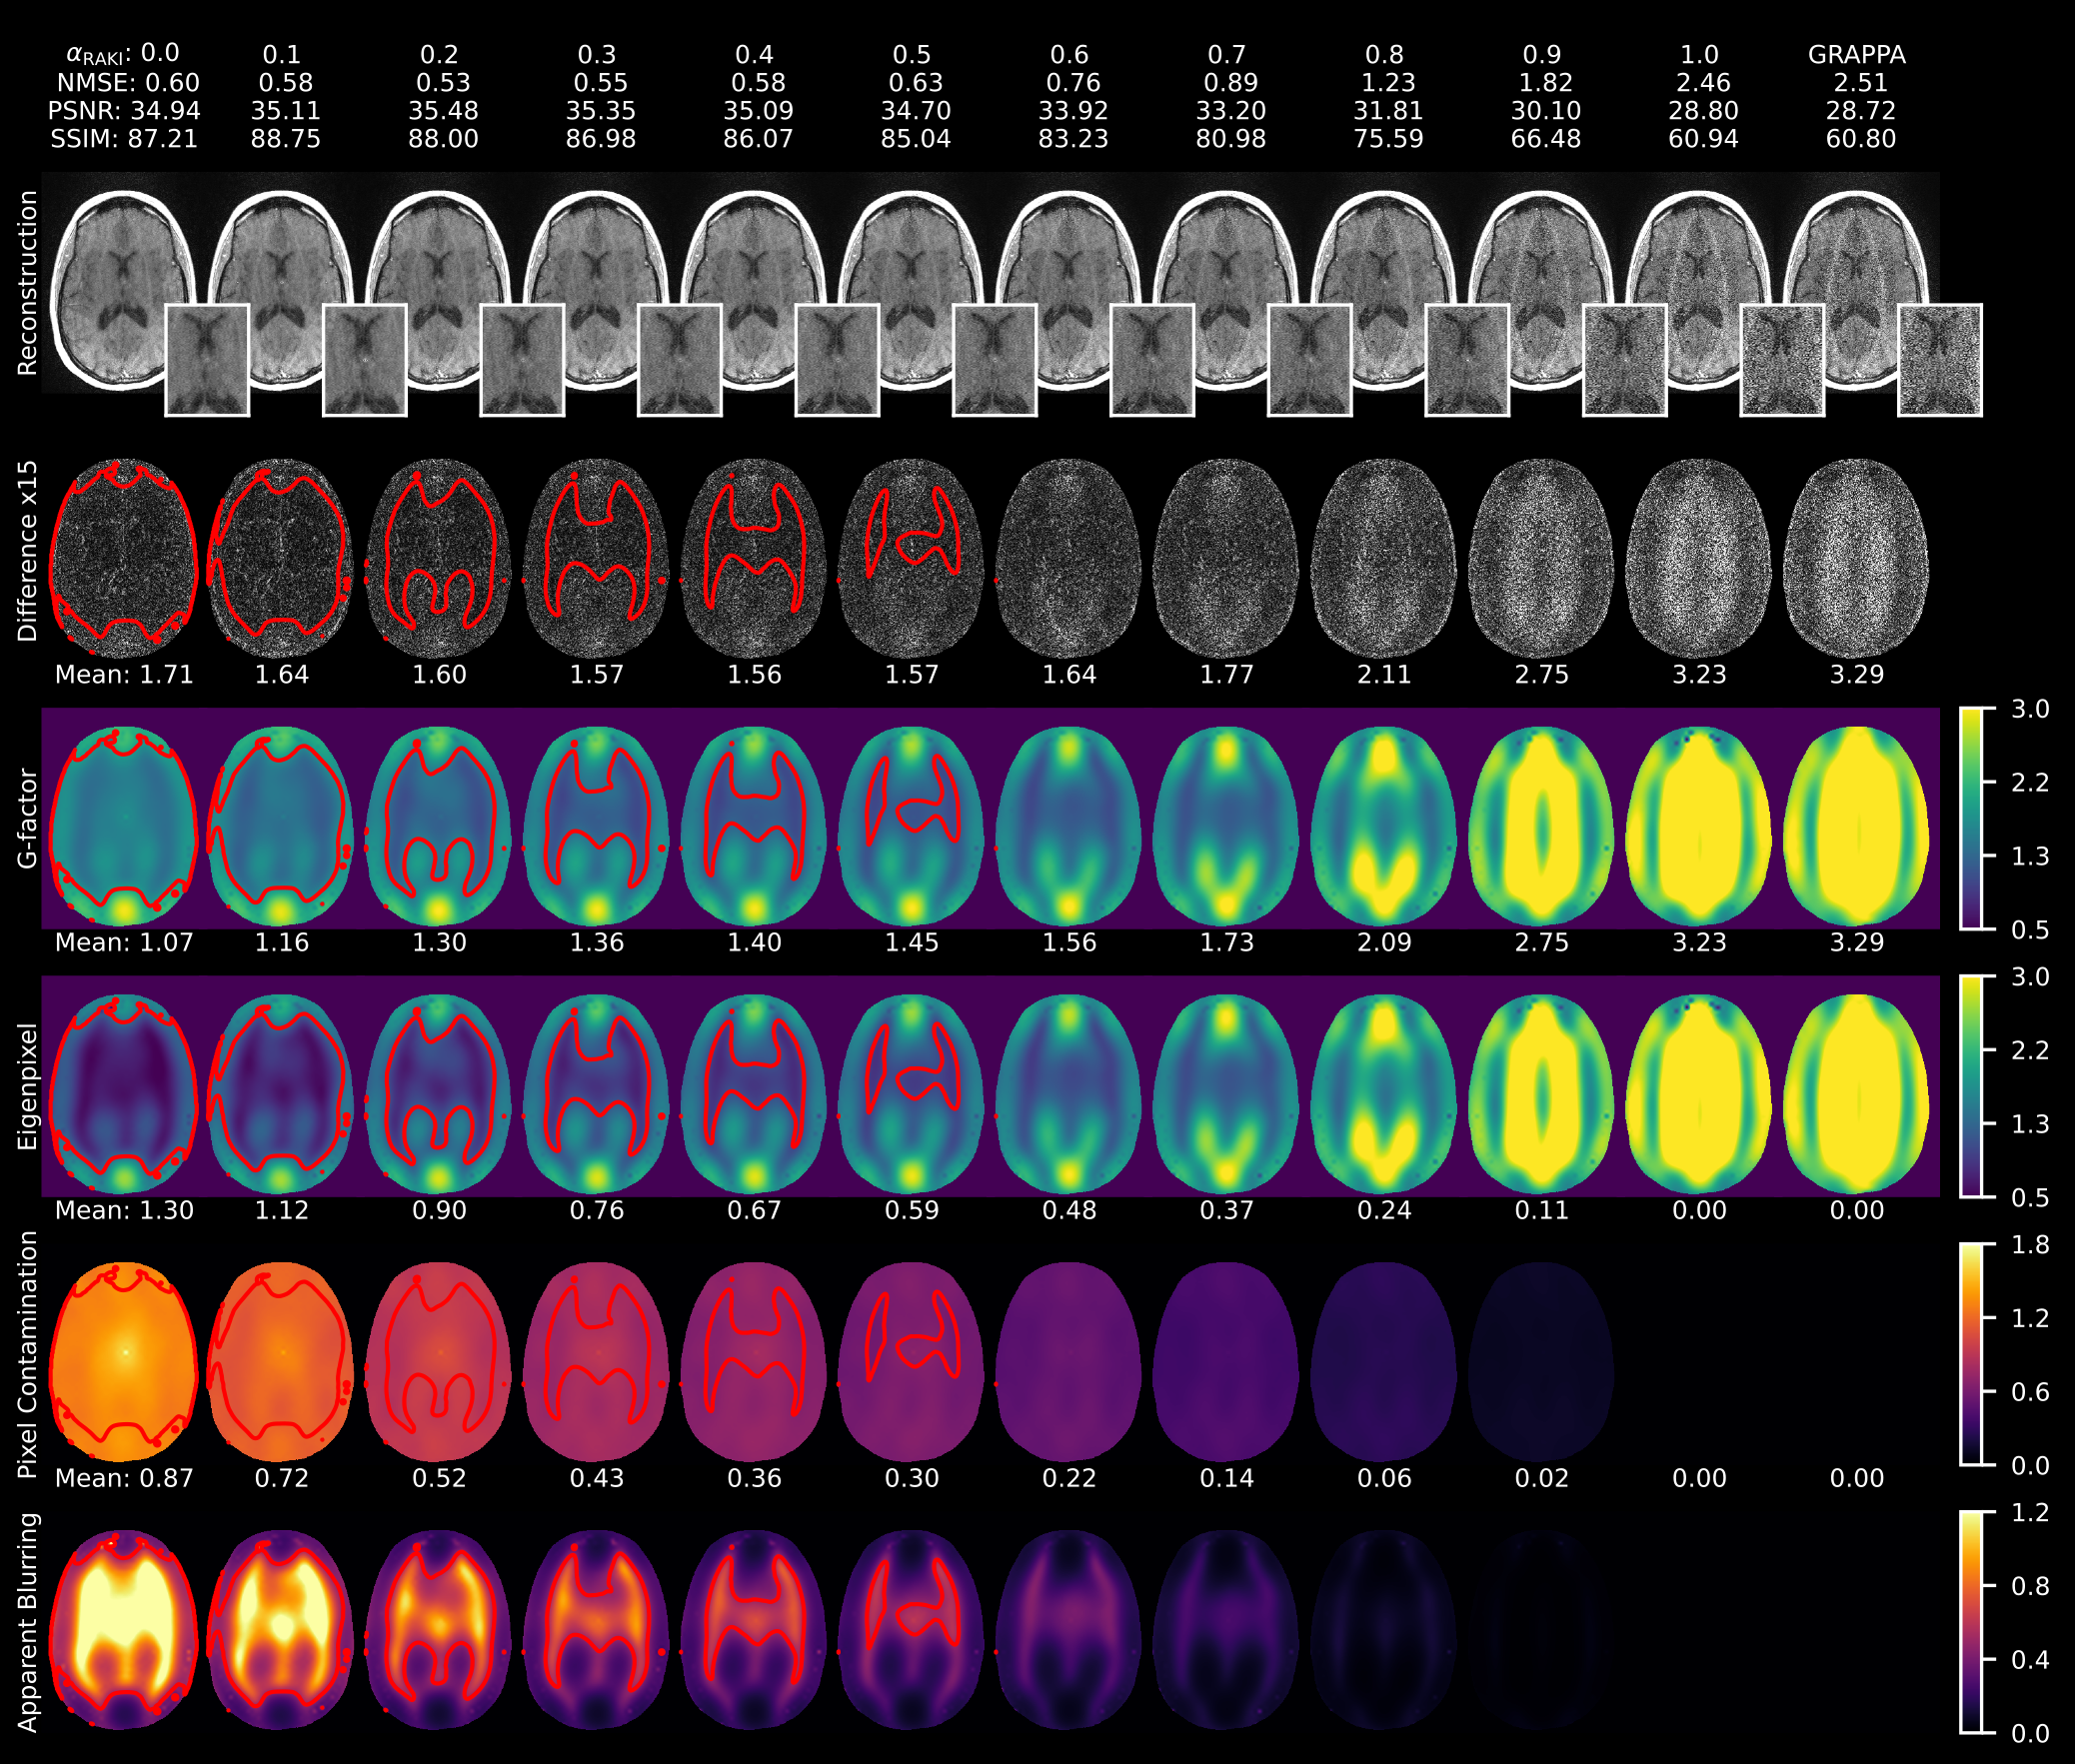

As demonstrated in Figure 5 for the nonlinearity sweep α{0.0,0.1,0.2,,1.0}\alpha\in\{0.0,0.1,0.2,\dots,1.0\}, pixel contamination contributions remain negligible in the linear regime but become dominant under strong nonlinearity. A balanced regime emerges near α0.5\alpha\approx 0.5, where eigenpixel contributions are still dominant and pixel contamination provides beneficial denoising. The distinct blurring sensation is quantified by the apparent blurring maps, becoming strong in the central ROI for highly nonlinear cases but still negligible around the edges. This coincides with the strongly denoised regions visible in the difference maps, closely following the red contour line. In highly nonlinear cases, the eigenpixel maps may locally drop below one, while an increase in pixel contamination indicates that it compensates for this suppressed eigenpixel signal contribution.

Similar trends are observed for acceleration factors R{2,3,4,5,6}R\in\{2,3,4,5,6\} when analyzing mean values of the respective variance maps over the whole brain and the central ROI (Figure 6, left and right columns, respectively). The means of the total and linear variance increase as nonlinearity decreases, showing a strong dependence on the acceleration factor. In contrast, pixel contamination is largely independent of acceleration factor and is modulated primarily by nonlinearity level (Figure 6 A and D). Due to the interplay of these competing processes, a trade-off between denoising and apparent blurring emerges for a given undersampling factor, reflected by the convex shape of the g-factor curves within the moderately nonlinear regime α0.5\alpha\approx 0.5. Here, the mean apparent blurring remains moderate (gblur0.5g_{\text{blur}}\approx 0.5) (Figure 6 B and E). SSIM promotes image smoothness driven by high nonlinearity levels, which then degrades substantially in the linear regime, especially for high undersampling factors R{4,5,6}R\in\{4,5,6\} (Figure 6 E and F). This is accompanied by high apparent blurring reducing the total and linear variances. However, this denoising is not spatially uniform but occurs predominantly in the central region. Steeper curves at linear and nonlinear extremes for high undersampling factors R{4,5,6}R\in\{4,5,6\} indicate this when comparing whole brain and ROI indices (left and right panels).

RAKI and GRAPPA reconstructions, ×15\times 15 magnified difference maps, generalized g-factor, eigenpixel, pixel contamination, and apparent blurring maps are shown for LReLU\mathbb{C}\text{LReLU} factors α{0.0,0.1,0.2,,1.0}\alpha\in\{0.0,0.1,0.2,\ldots,1.0\} with R=5R=5 and ACS=48ACS=48. Mean variances computed within the whole brain are displayed above each subfigure. The difference maps and aggregate quality metrics motivate the use of higher nonlinearity levels for improved denoising, as confirmed by the decreased g-factor values. The variance maps illustrate the composition of the g-factor: pixel contamination contributions remain negligible in the linear regime (α1.0\alpha\approx 1.0), but become dominant under strong nonlinearity (α0.0\alpha\approx 0.0), producing a noticeable blurring effect. This is reflected in the considerable drop of the eigenpixel contribution in the g-factor. An intermediate nonlinearity level (α0.5\alpha\approx 0.5) achieves the best balance between effective denoising and acceptable apparent blurring. The apparent blurring maps capture the visual effect of the dominant pixel contamination in the total variance, denoted by red contours for 𝐠blur=0.5\mathbf{g}_{\text{blur}}=0.5. The case α=1\alpha=1 corresponds to a RAKI network with linear activations, where pixel contamination is within numerical precision. In this purely linear case, the total variance equals the eigenpixel map, consistent with GRAPPA behavior. NMSE: normalized mean squared error (×100\times 100), PSNR: peak signal-to-noise ratio, SSIM: structural similarity index (×100\times 100).